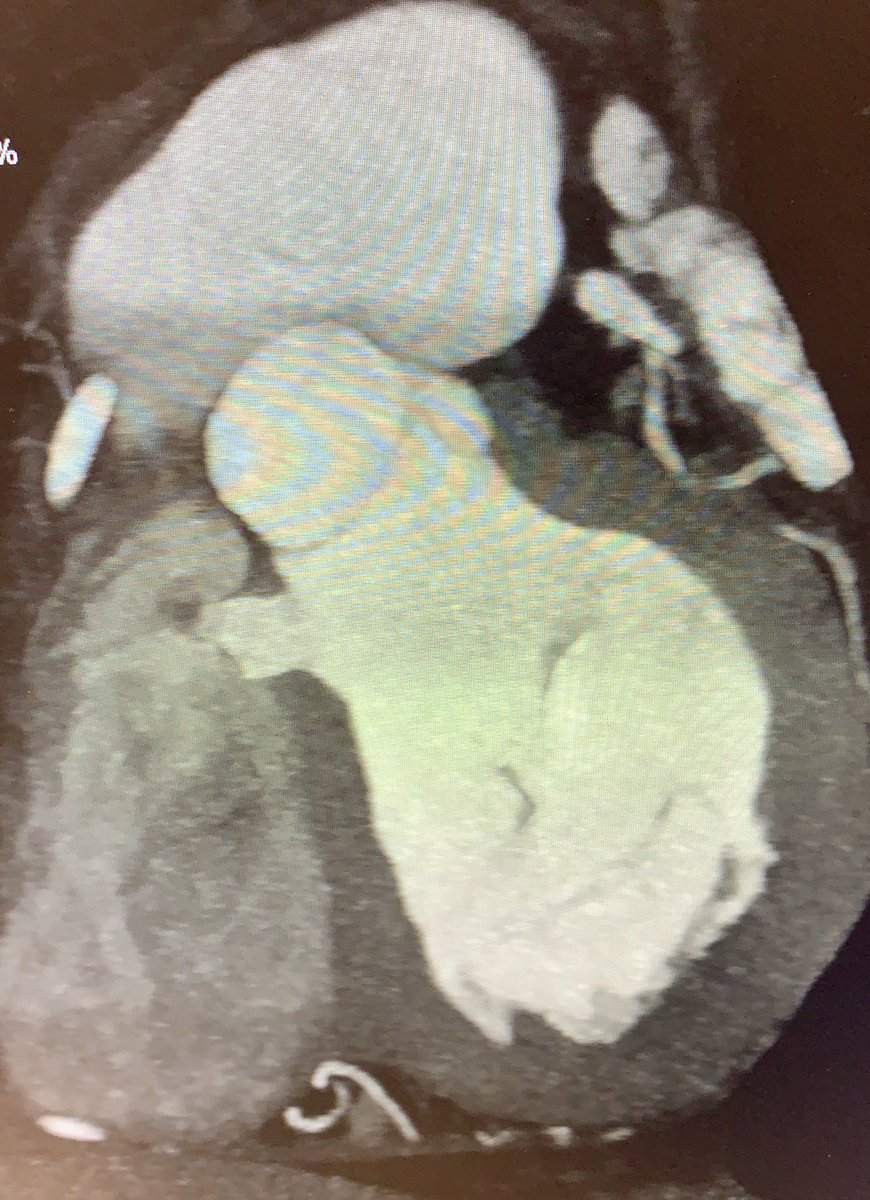

75 yo M presented late with Ant wall MI, echo suspected large contained rupture/ pseusoaneurysm confirmed on CT. Awaiting surgery @nicvd_karachi @alexsfelixecho #echofirst @iamritu @m_naeem_88 @Heart_SCCT @AJamilTajik @NicvdImaging #multimodalityimaging